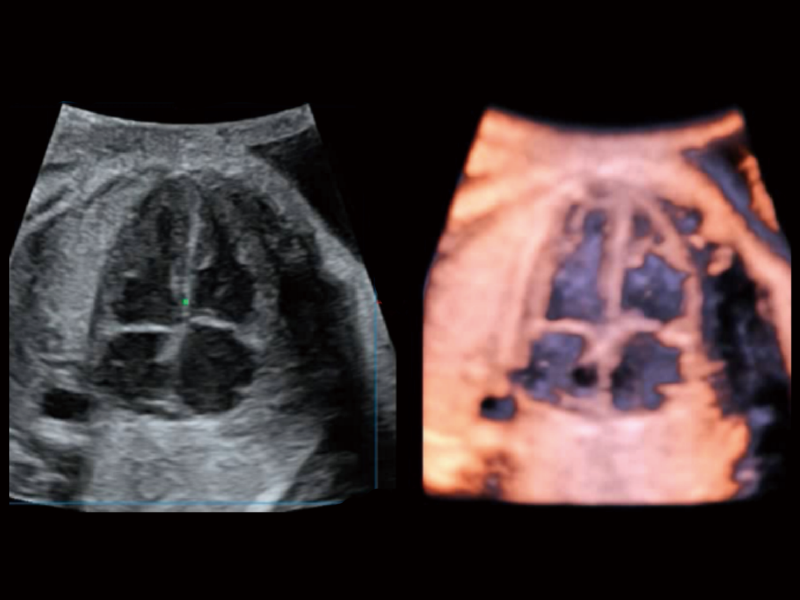

在傳統(tǒng)血流的基礎(chǔ)上優(yōu)化掃查和算法策略,能夠更好的抑制組織信息,提煉紅細(xì)胞運(yùn)動(dòng)信息,得到更高幀頻,高靈敏度和分辨率的血流信號(hào),還原更真實(shí)的血流動(dòng)力學(xué)。

通過(guò)光照模型,使二維血流顯示出立體的效果,增加血流的敏感性、成束性,減少外溢。可以和其他不同的血流技術(shù)聯(lián)合使用,融合不同技術(shù)的優(yōu)勢(shì)。輕松應(yīng)對(duì)微小血管,增強(qiáng)血流的立體效果,提升視覺(jué)敏感性。

通過(guò)創(chuàng)新的Matrix E自適應(yīng)濾波算法,能有效濾除軟組織和噪聲信號(hào),最大限度保留超低速微細(xì)血流的信號(hào);結(jié)合超長(zhǎng)時(shí)間域算法,極大提升細(xì)微血流的敏感性和空間分辨率,更真實(shí)的反應(yīng)組織、包塊的血流灌注情況。